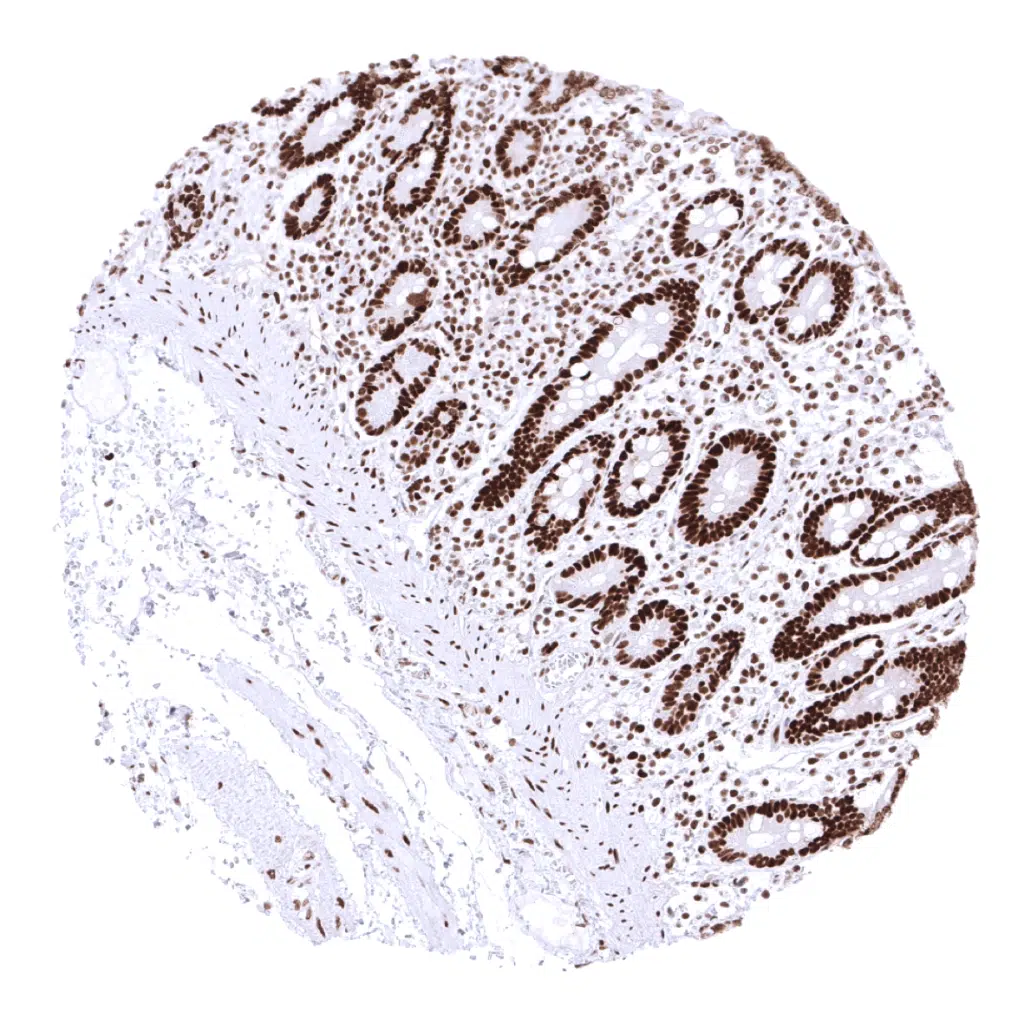

Colon, mucosa – In the colon epithelium, the MSH2 staining intensity decreases from the bottom to the top of the crypts.

Rectum, mucosa – In the colon (and rectum) epithelium, the MSH2 staining intensity decreases from the bottom to the top of the crypts.